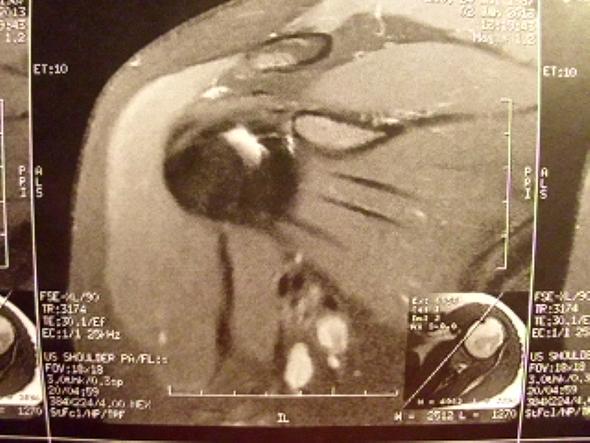

Nach der Operation kommt es auf die richtige Nachbehandlung an, um Rückschläge zu vermeiden. Dazu gehören: Die Patientendaten - Um den MRT-Befund später eindeutig einem Patienten zuordnen zu können, werden der Name des Patienten und meistens auch das Geburtsdatum und die. Mögliche Beschwerden in Folge einer Rotatorenmanschettenruptur sind u. a. - abhängig vom genauen Bild und Ausmaß der Verletzung - stechende Schmerzen, ausstrahlende Schmerzen in.